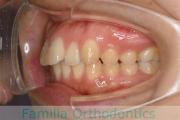

でこぼこを治したいということで来院されました。上下左右から親知らずも第一小臼歯も抜歯が必要で、歯科矯正アンカースクリューを併用して大臼歯を後ろに引っ張りながらの治療でした。3年弱、35回程度の通院が必要でした。

叢生が著しく、後戻りのリスクがあります。またアンカースクリューが必須のため、もしもスクリューが安定しないと、治療が難しく長くなってしまう恐れがありましたが、幸い脱落は見られませんでした。